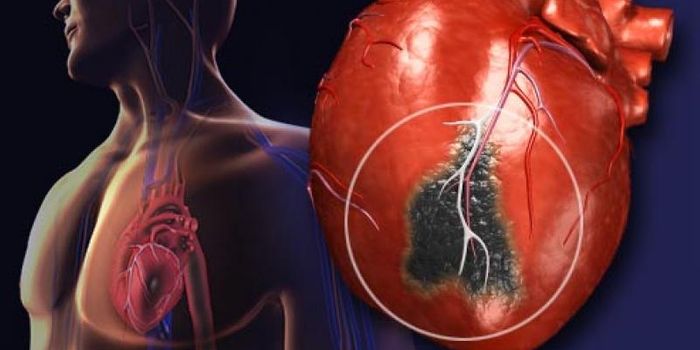

OCT 02, 2017Clinical & Molecular DXInstead of the usual hour-long wait for routine lab results, a new blood test could allow doctors to diagnose a heart at ...